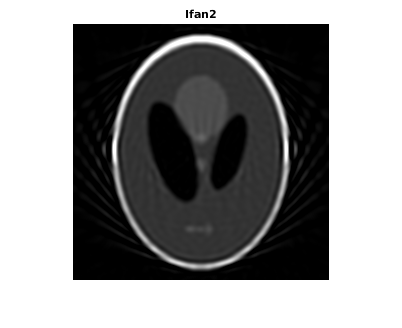

Восстановите изображение от данных о проекции луча вентилятора с помощью ifanbeam. В каждой реконструкции совпадайте с интервалом датчика вентилятора интервалу, используемому, когда данные о проекции были созданы ранее. Пример использует параметр OutputSize, чтобы ограничить выходной размер каждой реконструкции совпадать с размером оригинального изображения P. В выводе отметьте, как качество реконструкции поправляется как количество лучей в увеличениях проекции. Первое изображение, Ifan1, было создано с помощью 2 интервалов степени лучей; второе изображение, Ifan2, было создано с помощью 1 интервала степени лучей; третье изображение, Ifan3, было создано с помощью 0,25 интервалов лучей.

Ifan2 = ifanbeam(F2,D, ... 'FanSensorSpacing',dsensor2,'OutputSize',output_size); figure, imshow(Ifan2) title('Ifan2')